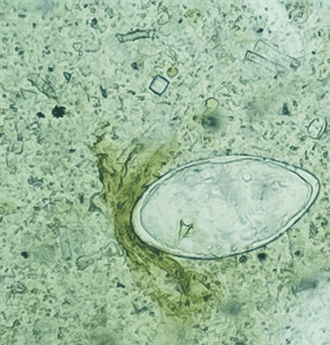

이 지역 아이들의 건강을 위협하는 대표적인 질환은 주혈흡충(SCH)과 토양 매개성 기생충(STH)입니다. 이 질환들은 단순한 감염을 넘어 아이들의 성장과 학습, 나아가 삶의 기회 자체를 제한하는 요인이 됩니다.

또한 현장에서 진행 중인 대변·소변 채취 과정을 함께 관찰하며 검사 절차가 안전하고 정확하게 이루어지고 있는지도 점검했습니다. 이는 향후 감염 모니터링 체계를 더욱 안정적으로 운영하는 데 필요한 중요한 과정이었습니다.